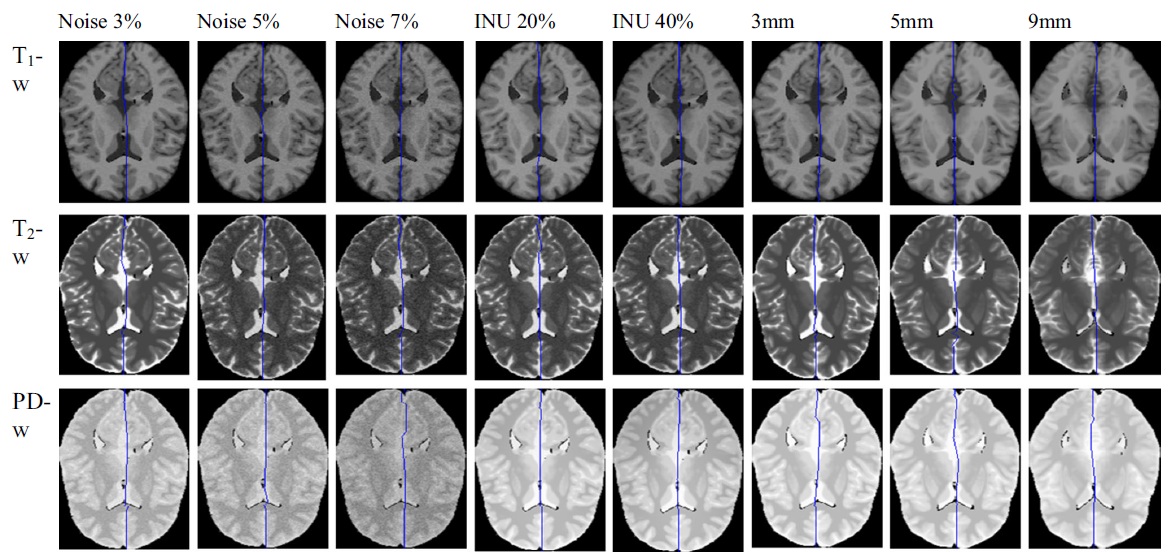

Owner: Griffith University, Gold Coast

Developed advanced 3D MRI brain segmentation models using Genetic Algorithms, unsupervised clustering techniques (Fuzzy C-Means, KNN, K-Means), and mid-sagittal surface detection for medical imaging research.